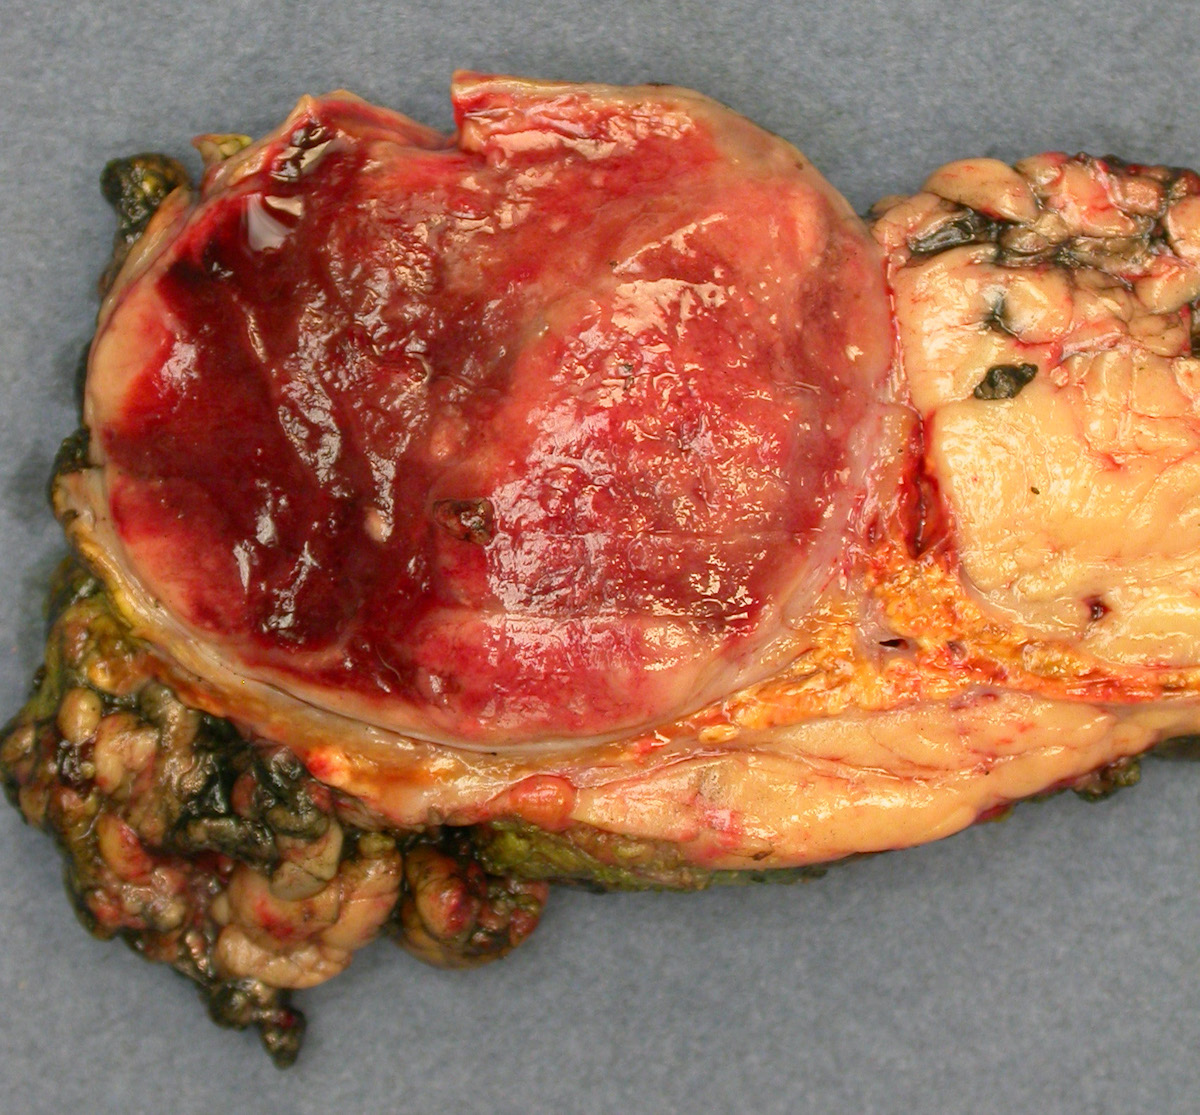

Gross description

- Firm, well circumscribed to infiltrative and partially encapsulated or pseudoencapsulated (Mariani-Costantini: Carotid Body and Vagal Paragangliomas - Epidemiology, Genetics, Clinicopathological Features, Imaging, and Surgical Management [Accessed 4 November 2021])

- Varies from dusky brown to red, gray or tan cut surface (J Radiol Case Rep 2019;13:19)

- Hemorrhage and cystic degeneration may be present

Gross images